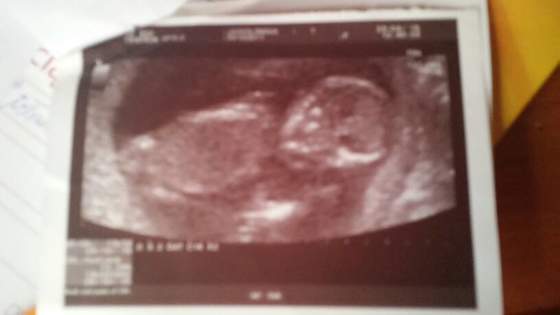

Kasiu juz widziałam i raczki i nóżki: ) wstawie zdhecie z 23 kwietnia ale dosc kiepskie :( ogolnie ok.... tzn juz jest ok :)

Załączniki

• 1430760952577.jpg

1430760952577.jpg

12,3 KB · Wyświetleń: 50